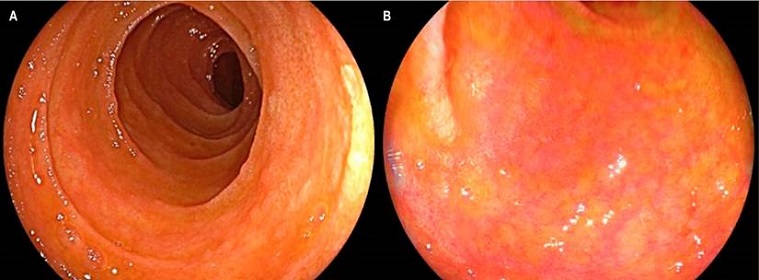

Se trata de un paciente masculino de 26 años con diagnóstico de leucemia linfoblástica aguda de células B quien recibió terapia de inducción con protocolo PETHEMA-LAL de alto riesgo y 3 ciclos de consolidación con PETHEMA; posteriormente presentó una recaída sistémica con compromiso en el sistema nervioso central, por lo que se administró quimioterapia de alta intensidad con IDA-FLAG, citarabina y terapia intratecal y se logró la remisión morfológica con enfermedad residual medular, por lo que requirió una nueva quimioterapia con miras para trasplante de médula ósea (TMO). Se realizó el trasplante haploidéntico de progenitores hematopoyéticos con su madre como donante. Ingresó al día 24 de trasplante por diarrea aguda, ictericia mucocutánea generalizada y exantema macular eritematoso difuso con descamación. En los paraclínicos se observó pancitopenia y perfil hepático alterado con patrón mixto (hepatocelular y colestásico). Ante la sospecha de EICH se inició el manejo empírico con dosis altas de metilprednisolona y se solicitaron estudios endoscópicos. La esofagogastroduodenoscopia (EGD) demostró como hallazgos relevantes mucosa de primera y segunda porción duodenal con zonas focales de atrofia en parches y ausencia de vellosidades, sin cambios inflamatorios, con mucosa gástrica normal (Figura 1).